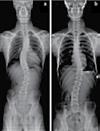

No. 1086 Thursday July 27, 2023 l ColoradoTimesNews.com 43 교통사고 후유증 / 목 통증 / 목 디스크 / 오십견 / 어깨통증 말초신경장애: 손, 발, 다리의 통증, 저림, 근육약화감, 감각상실 (편)두통 / 불면증 / 어지러움 / 턱관절 장애(TMJ) 척추측만증(Scoliosis) / 척추협착증 / 허리수술 후유증 허리통증 / 허리 디스크 / 관절염 / 좌골신경통 / 고관절, 발목, 손목 통증 ▪ ▪ ▪ ▪ ▪ ▪ ▪ ▪ ▪ 최첨단 목/허리 디스트 치료기기 최신형 디지털 X-ray 시설 Therapeutic Massage ▪초음파, 전기치료 Gonstead Chiropractic 교정치료 치료 진료과목 교통사고 치료 전문 자동차 보험 건강 보험 상해 보험 Southern California University of Health Science Doctor of Chiropractic 콜로라도주 척추신경 보드 정회원 캘리포니아주 척추신경과 보드 정회원 National Board 척추신경과 정회원 손석기 D.C. 원장, 척추신경 전문의 chiro1health@gmail.com Open Hours 월/수/금 9am-6pm 화/목: 2pm-6pm 청소년을 위한 척추교정 프로그램